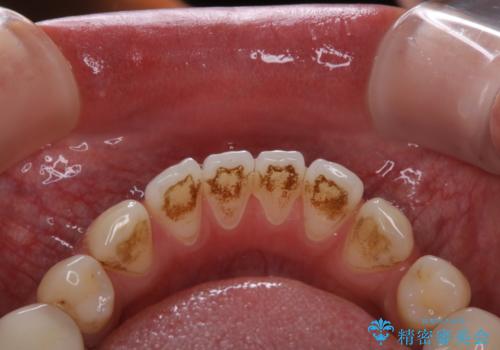

プラーク(細菌の塊)や歯石がたまると歯の表面はザラつきいてきます。そのザラつきは歯周病や虫歯菌の棲家となります。そのまま放置すると、歯肉が腫れてきたり、歯肉から出血したり、口臭が強くでたりします。とくに歯肉の境目は、歯磨きで汚れを除去することが難しく、プラーク(細菌の塊)や歯石が溜まりやすい場所です。

歯並が、がたついている場合はなおさら汚れが溜まりやすいです。矯正治療前や矯正中、定期的にPMTCをすることで、矯正治療中の歯肉トラブルを防ぐことにつながります。

- これから矯正治療を始めるため、今の状態でも歯をきれいにしておきたいとのことでした。PMTC60分コースを行いました。